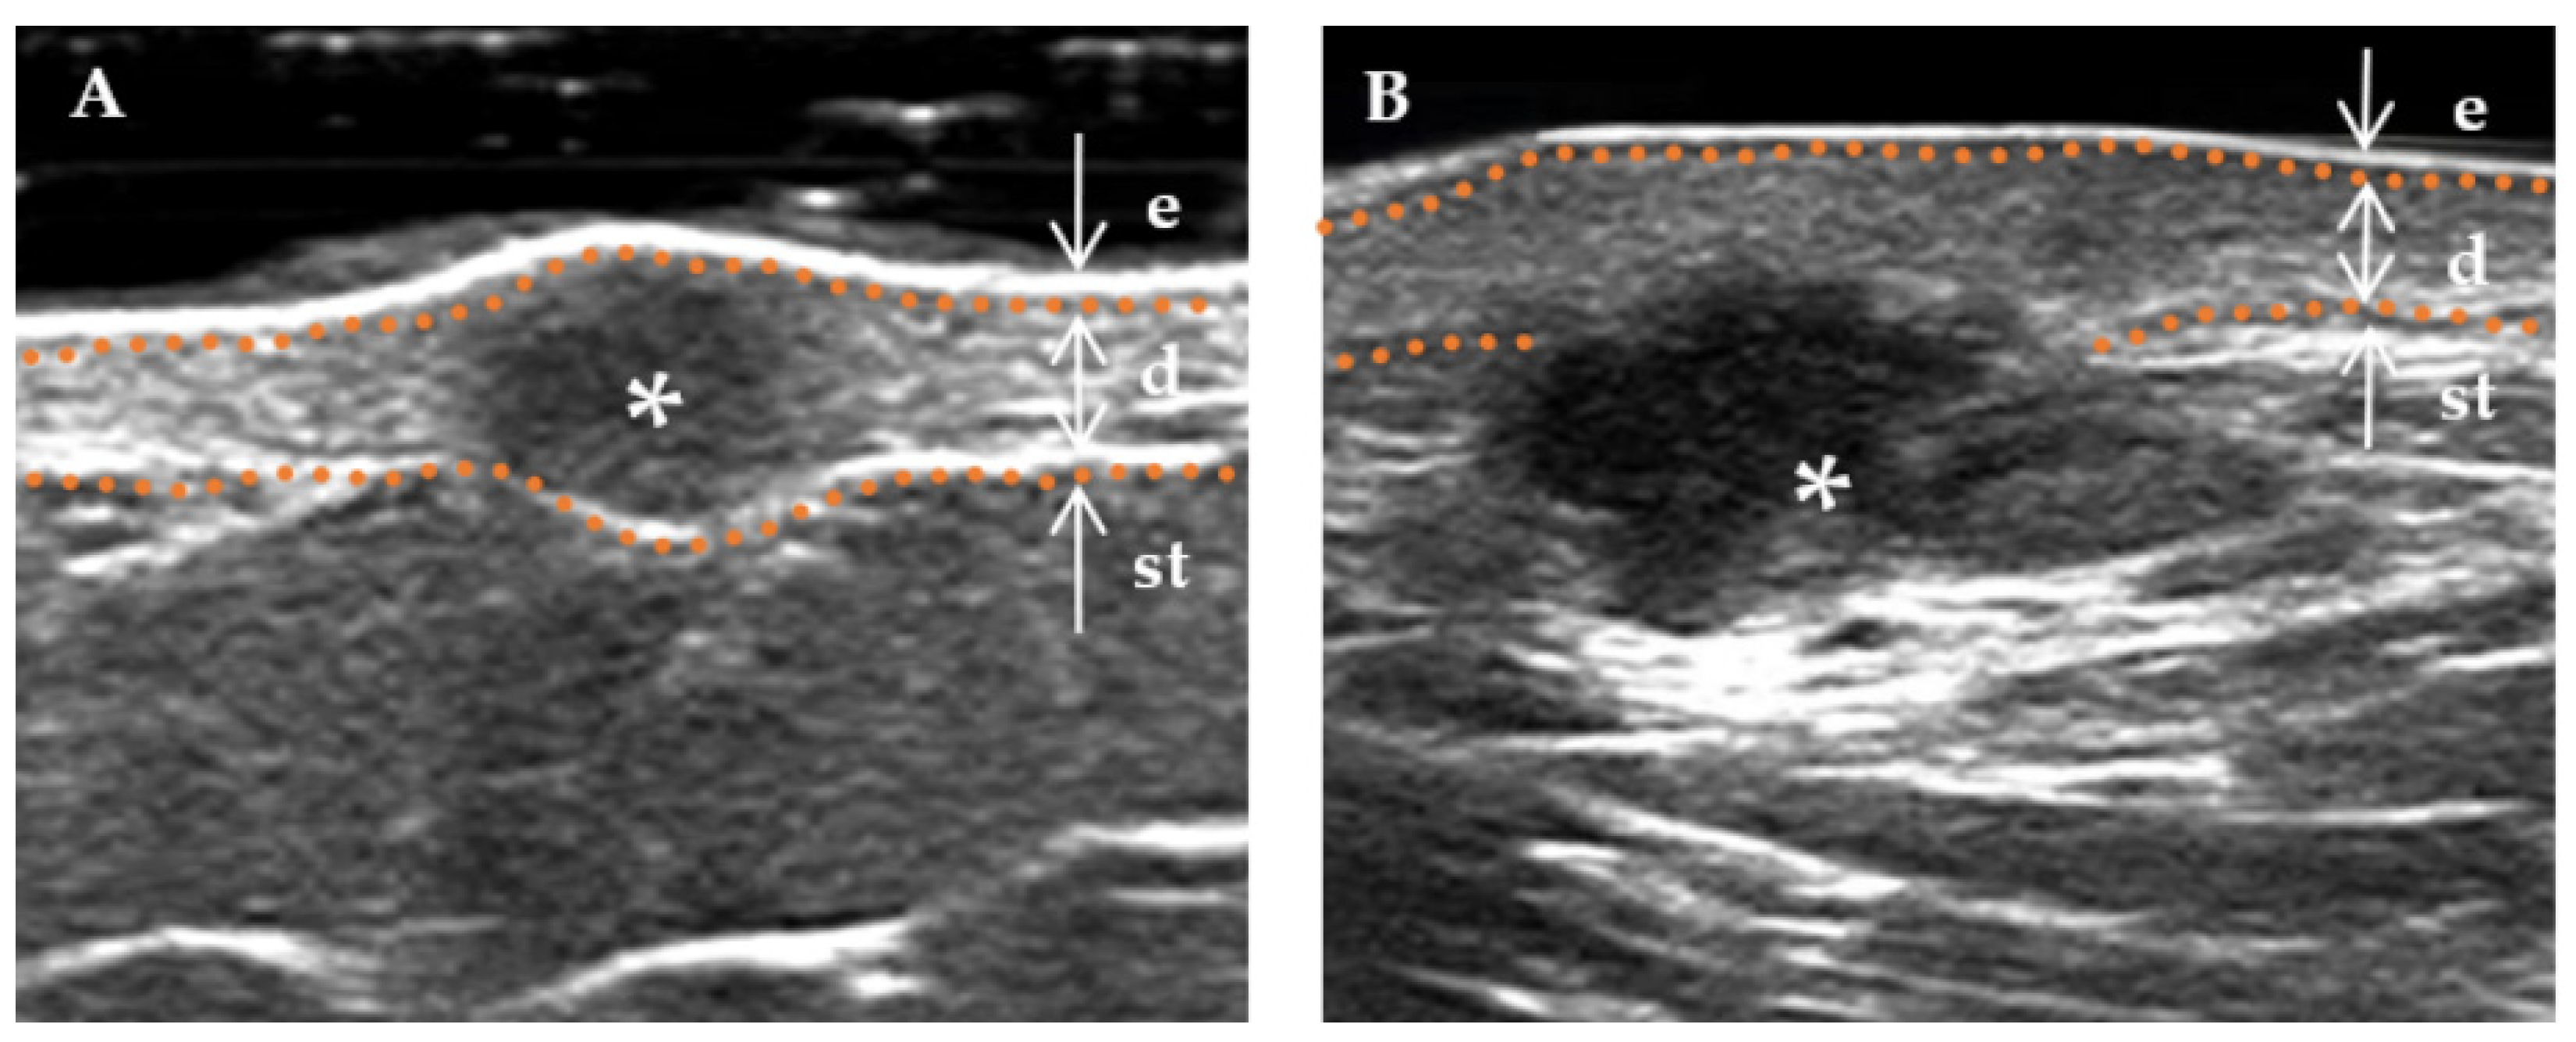

| Thickness a (mm) | 4.1 (3.2–6.1) | 3.1 (1.3–4.2) | 0.018 * |

| shape, n (%) | 0.001 * | ||

| Regular (incl. creeping) | 5 (29.4%) | 26 (78.8%) | |

| Irregularity | 12 (70.6%) | 7 (21.2%) | |

| Stratum basal, n (%) | 0.002 * | ||

| Dermis | 6 (35.3%) | 26 (78.8%) | |

| Subcutaneous | 11 (64.7%) | 7 (21.2%) | |